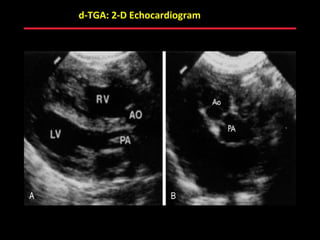

d-TGA: 2-D Echocardiogram

ABB MD